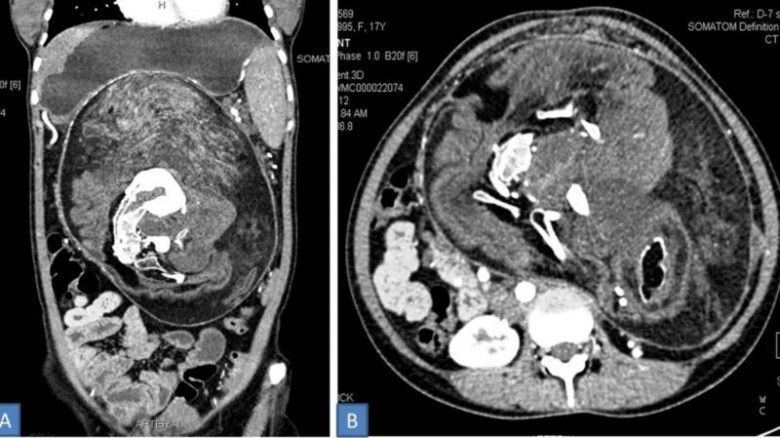

Selama lima tahun berikutnya, benjolan itu secara bertahap tumbuh besar dan menyebabkan rasa sakit secara berkala. Pada saat remaja berusia 17 tahun itu mengunjungi para dokter, dia tidak dapat makan banyak dan selalu merasa kenyang, kemungkinan karena benjolan itu mulai menekan organ-organ internalnya.

Pada pemeriksaan fisik awal, benjolan itu diduga tumor. Meskipun, memang yang dialami perempuan bisa dibilang sebagai tumor. Tetapi ketika mereka melakukan pemindaian CAT pada benjolan itu, mereka menemukan endapan kalsium yang terlihat seperti "bentuk tulang belakang, tulang rusuk dan tulang panjang," dan kebenaran yang lebih mengerikan akhirnya terungkap. Para dokter kemudian berusaha untuk mengeluarkannya.

Menurut laporan itu, isi tumor "terdiri dari rambut, tulang dewasa dan bagian tubuh lainnya." Bagian tubuh ini termasuk "banyak gigi dan struktur menyerupai tunas tungkai." Ukurannya yang tipis — 36 × 16 × 10 sentimeter — juga akan menjadikannya yang terbesar yang pernah ditemukan pada kasus janin dewasa dalam janin.